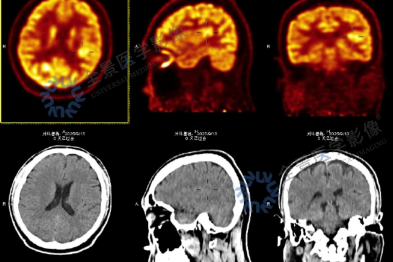

血糖越界,肾脏就会被「甜」坏?